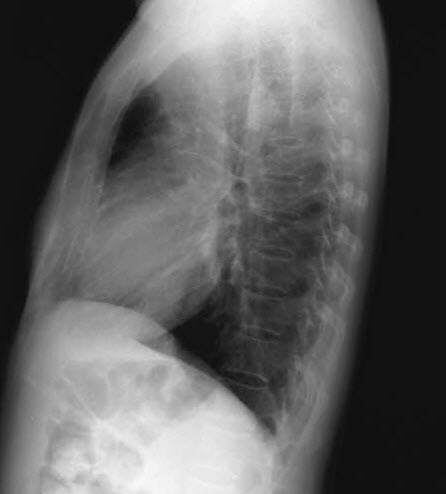

The patient was seen at a local urgent care center and treated with levofloxacin for a week. A chest radiograph showed infiltrates in the right upper lobe. The symptoms worsened and the medication was switched to clarithromycin, but there was no marked improvement.

A chest radiograph and sputum evaluation for acid-fast bacteria (AFB) are ordered.

A high index of suspicion is warranted. The diagnosis is confirmed by demonstration of AFB either in biopsy material or sputum, in conjunction with sputum culture. Chest radiography or CT can be helpful.